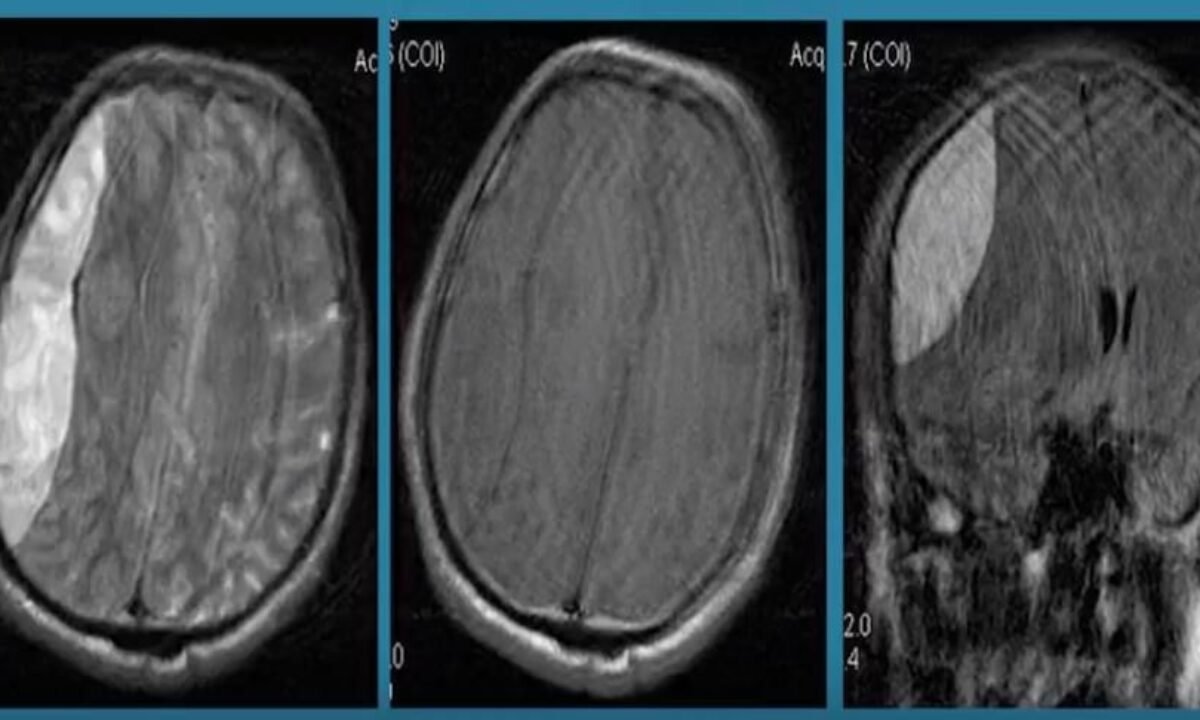

З діагностикою тут важливо діяти швидко. Як щось підозрюєте – звертайтесь до спеціалістів. Просто тримайте це в голові. Використовують рентген, комп’ютерну томографію (КТ) або магнітно-резонансну томографію (МРТ) для оцінки стану. І ось тоді – рішення. Складна операція? Може. Лікарські препарати? Авжеж, але залежить.